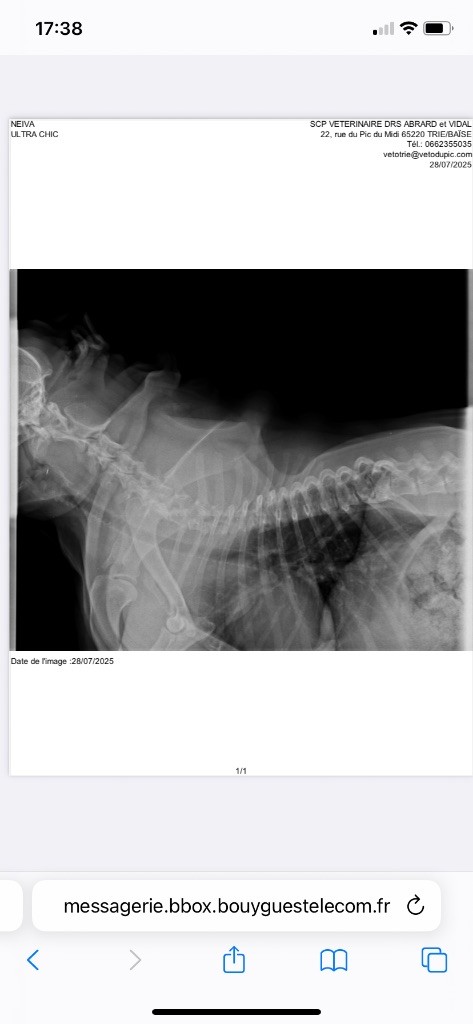

- Trachée normale avec comme mesures : 13 mm

28/7/2025 à Trie sur Baise ( 65220 )

Absence d hypoplasie de la trachée

Manifestion : Examen de la trachée - Juge : Docteur Martinez